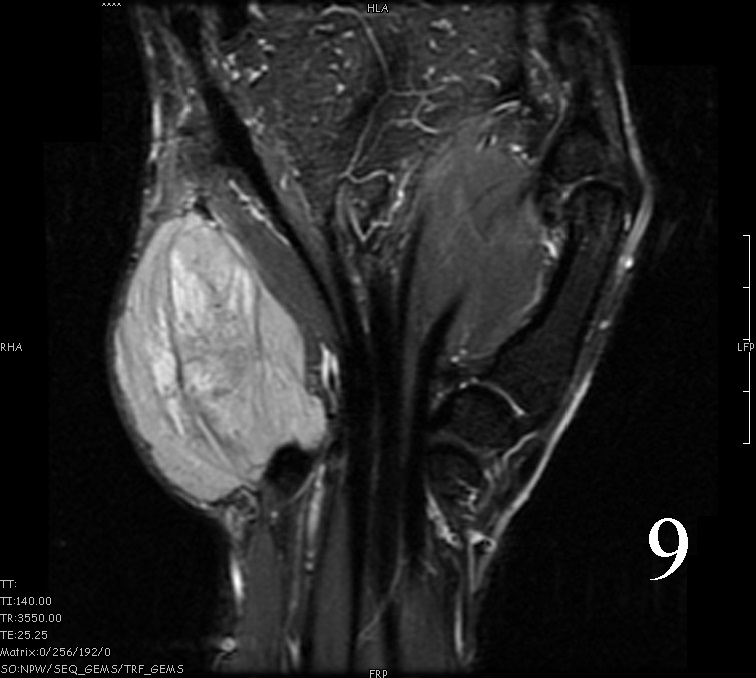

MRI

- Heterogeneous mass (does not follow signal of skeletal muscle)

- Isointense to skeletal muscle on T1 (Fig. 4, Fig. 5, Fig. 7, Fig. 8)

- Hyperintense signal on T2, sometimes low to intermediate signal on T2 if there is extensive fibrous tissue within the tumor (Fig. 6, Fig. 9).

- Prominent vascularity

- Deep enhancement with gadolinium

- Possible extensive hypercellular fibrous tissue and hemosiderin seen on T2

Fig. 4-9: MRI of a rhabdomyosarcoma of the hand. The MRI is nonspecific and shows a heterogeneous mass particularly on postgadolinium images T1 W images (Fig. 8) and T2 W images (Fig. 9).